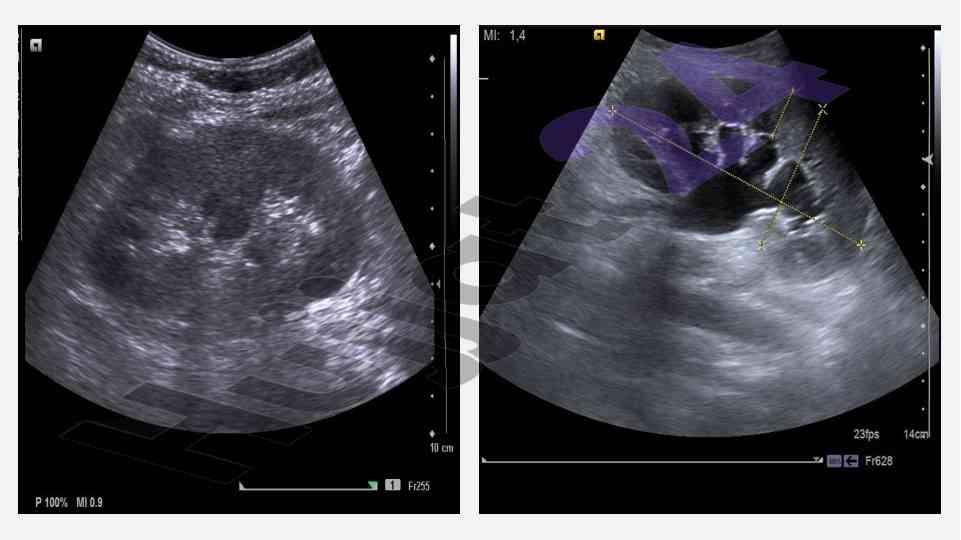

Ushbu maqola buyrak va siydik yo'llari nurli tekshirish usullarini, jumladan, sonografiya va ekskretor urografiyani, ularning afzalliklari va kamchiliklarini o'rganadi.